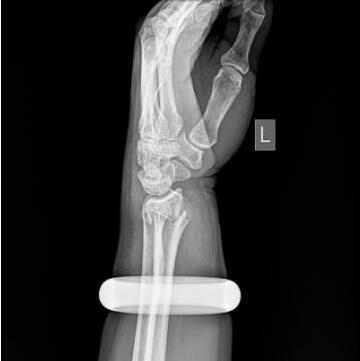

25日早上,57岁的王女士买菜回家时不慎滑倒,情急之下她用左手撑地,很快手腕就肿了起来。邻居听说后,让她赶紧去做做按摩,结果越按越痛,越肿越厉害。下午她找到武汉市第一医院骨科门诊,拍片发现左手桡骨远端骨折。

此时,手镯卡住腕部,不但会加重局部肿胀,还会越勒越紧导致肢体坏死。管床医生石晨尝试用肥皂水、润滑剂等方法取镯,都没能成功。

玉镯贴身戴了七八年,当年花了2万元买的。思虑再三,王女士提出砸碎玉镯,并签字为证。石晨用叩诊锤敲碎了镯子后,当即为她手法复位,打上了石膏。